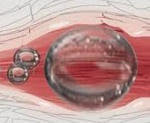

Согласно классической теории, жировая эмболия — результат прямого попадания частичек костного мозга в кровоток в момент получения травмы. Далее глобулы с током крови распространяются в организме. При размере частиц >7 мкм они вызывают закупорку легочных артерий. Мелкие капли жира минуют легкие и проникают в кровеносную сеть головного мозга. Возникает церебральная симптоматика. Существуют и другие предположения относительно механизмов развития процесса.

- Лабораторная диагностика. Определенное диагностическое значение имеет выявление в плазме липидных глобул размером 7-6 мкм. Предпочтительнее забирать биоматериал из магистральной артерии и центральной вены. Исследование сред из обоих бассейнов проводят по отдельности. Выявление глобул повышает риск развития окклюзии, однако не гарантирует ее возникновения.